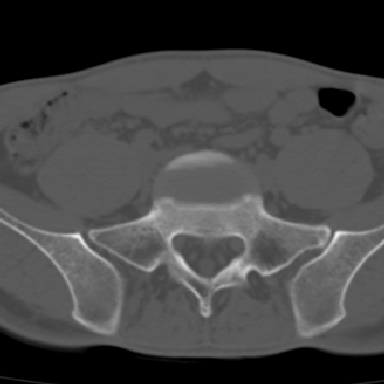

m 30 腰背部不适半年; 清晨时僵硬; 活动症状有所改善

双侧骶髂关节下2/3关节面模糊,毛糙,可见小囊状骨质破坏区.支持强直性脊柱炎.

强直性脊柱炎的早期改变!不仅表现为双侧骶髂关节,第5腰椎与骶椎间的关节突关节也有类似改变。

双侧骶髂关节下2/3关节面模糊,毛糙,髂骨侧可见小囊状骨质破坏区,骶髂关节间隙增宽(软骨破坏期)。支持早期强直性脊柱炎。

双侧骶髂关节下2/3关节面模糊、毛糙,可见小囊状骨质破坏区,呈虫咬状改变,周围可见增生硬化.支持强直性脊柱炎早期表现.